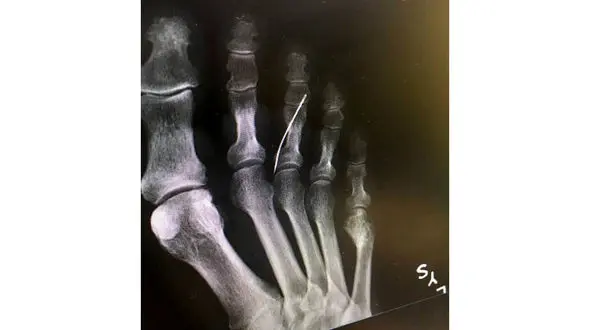

رکنا: بی خبری پیرزن از سوزنی که داخل بدنش بود وی را راهی بیمارستان کرد.